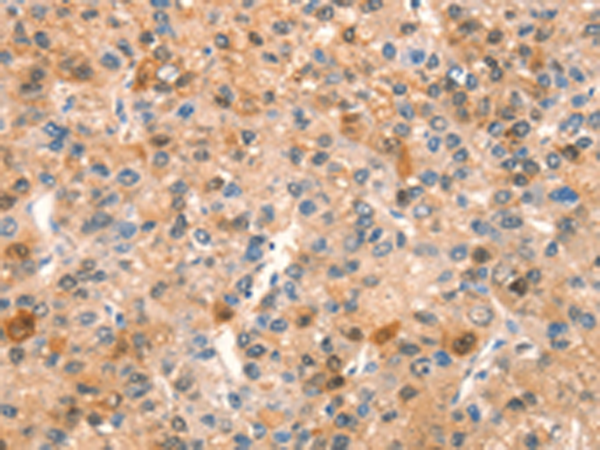

分类: 科研抗体货号: P11098别名: PAG, PAGA, PAGB, PRX1, PRXI, MSP23, NKEFA, TDPX2, NKEF-A应用: WB,IHC反应种属: Human, Mouse, Rat